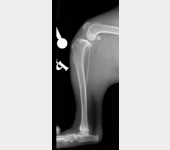

Nazywam się JJ :) Nigdy nie sądziłem, że będę potrzebował Waszej pomocy. Mam dopiero rok, urodziłem się 14 kwietnia 2019 roku. Lubię biegać, popiardywać, walczyć z odkurzaczem i dawać buziaczki człowiekom. Moi kochani opiekunowie przygarnęli takiego klopsa jakim jestem (a raczej byłem) ja... Mając zaledwie 4 miesiące zachorowałem na parwowirozę. Moje człowieki zrobili i oddali wszystko co mogli dać, abym wyzdrowiał. I tak się stało! Jednak zacząłem chorować bardzo szybko i po cichutku. Zaczęły boleć mnie moje tylnie nogi. Starałem się biegać, ale moje kolanka za bardzo bolały, więc ograniczyłem używania tylnich nóg do minimum podczas biegania. Żeby wejść na kanapę muszę bardzo się wysilić lub prosić moich człowieków, aby mi pomogli. Nie jestem w stanie wejść ani zejść po schodach bez odpoczynku. Moi kochani bracia i siostry (bo jesteśmy liczną rodzinką) patrzą na mnie z przykrością... Moje nietypowe siadanie na boku zaciekawiło domowników. Musiałem stworzyłem sobie garb, aby odciążyć nogi. Później pojawiły mi się guzki na prawej i lewej nodze. Na lewej nóżce guzek był troszkę większy, więc od razu pojechaliśmy do weterynarza. Niedobrze, bo guzki były już troszkę duże... Zapalenie, a może początek raka. Moja nowa Pani weterynarz zaczęła podejrzewać dysplazję biodrową. To mogłoby wyjaśnić moje “dziwaczne” siedzenie. Jednak nie była pewna, więc wysłała nas do specjalistów. Tam zrobili mi zdjęcia rentgenowskie i trochę mnie powyciągali. Bardzo mnie to bolało. Czułem wszystko, pomimo Jasia, którego dostałem. WERDYKT: Ześlizg główek w kościach kolana lewego i prawego o 33%, a to podobno bardzo dużo. Moje guzki to skutek rozlanego płynu zapalnego w kolanach. Moje lewe kolano choruje bardziej niż prawe. Jak się okazało nie urodziłem się z tym, ani nie jest to genetyczne. Po prostu zachorowałem na to. Moje kochane człowieki dostały dwie opcje.